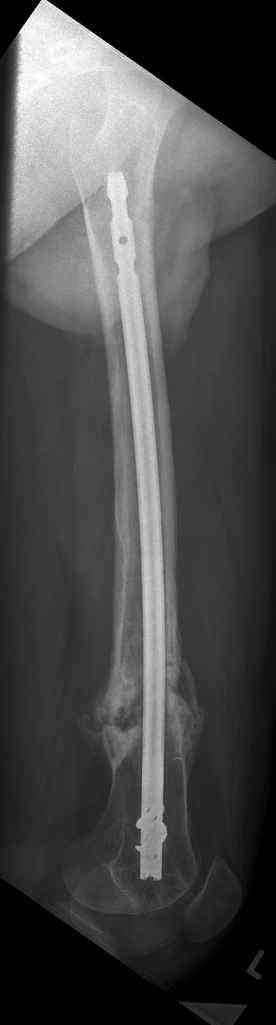

16 yr old boy, high energy motorcycle trauma trauma in July 2005 with:

- hip dislocation + acetabular fracture L

- distal femoral fracture L

- tibial shaft fracture L

- metatarsal fractures L

july 05: LISS femur, LCP plate tibia, double recon. plate post. acetabulum

feb 07: retrograde nail + bone graft + BMP

may 07: dynamisation nail

sept 07: locking screw removal (max. dynamisation reached)

nov 07: persistant non-union distal femur; other fractures healed

uneventfully.

All with gradual/partial weightbearing etc. Currently 50-100% weight

bearing, no pain.